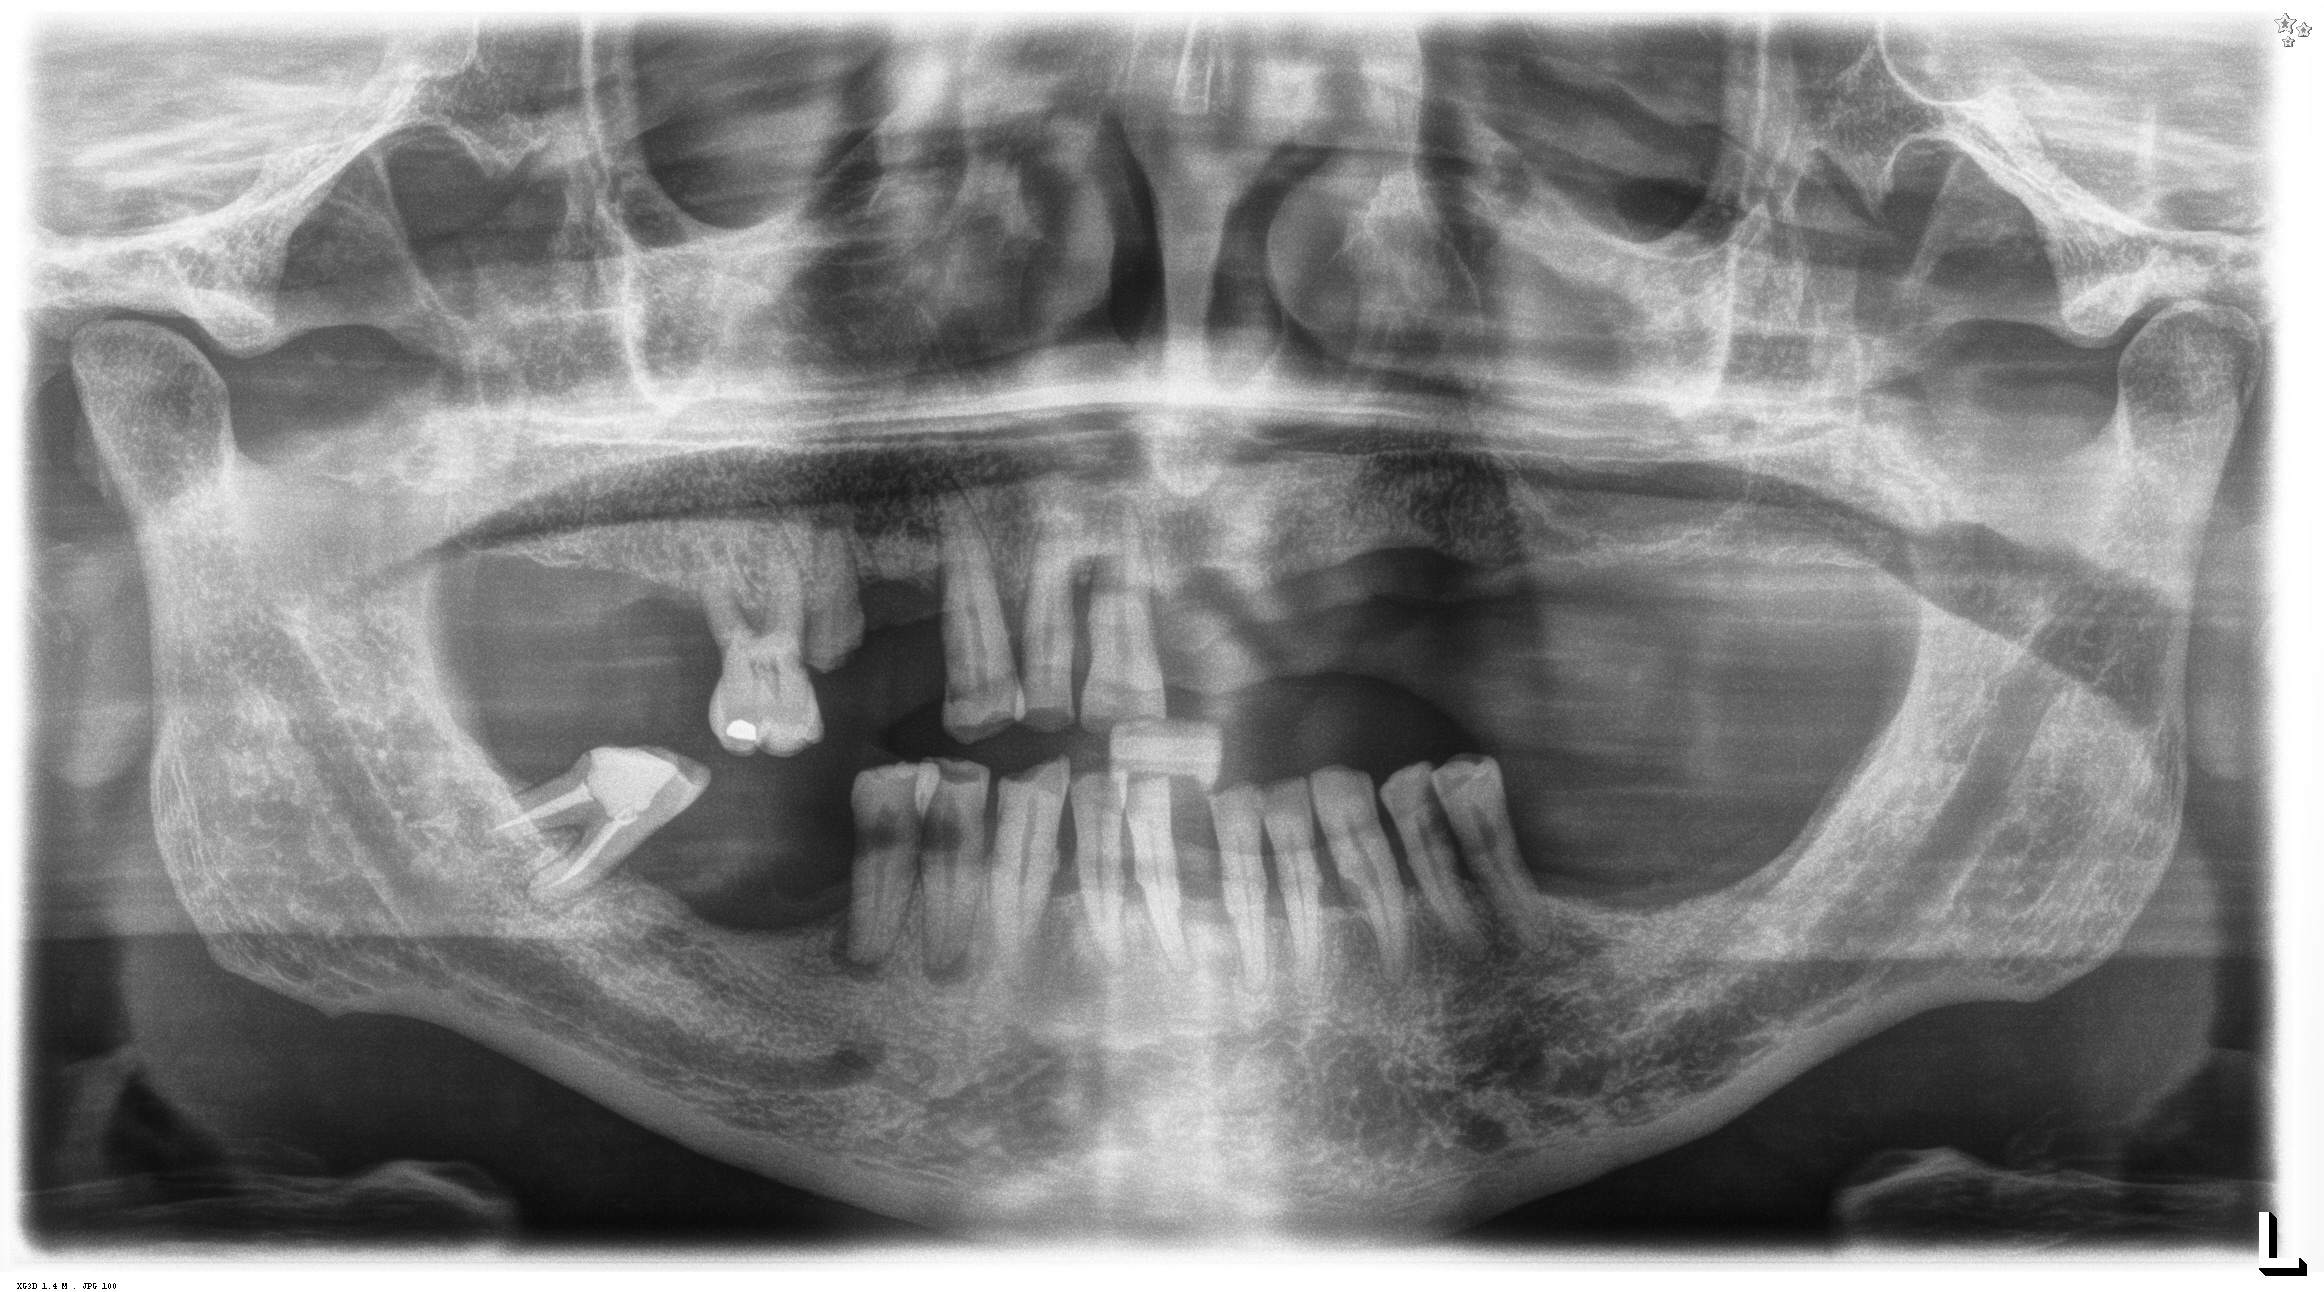

Domande di Dentisti-Italia.it | Pag. 163 (da 196 a 200)